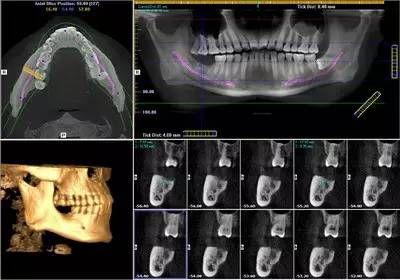

由于XG 3D/Ceph分辨率高,可以分辨人體組織內細微的差別,使影像診斷的范圍大大擴大。尤為重要的是8*8cm視野的掃描一次即可對口腔上下頜全部的組織及上頜竇腔及下頜神經管結構進行重建,為出診患者的綜合觀察及常規(guī)攝影提供了支持。